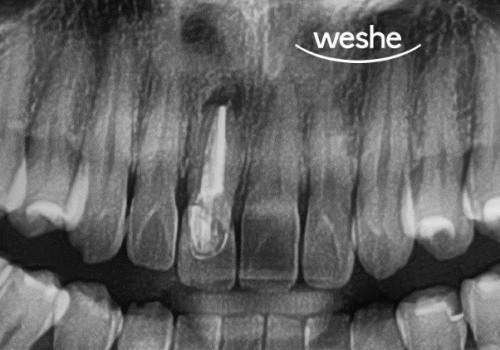

- 예시 사진을 통해 보는 검진 과정

발산 치과 에서 준비한

초진 엑스레이 사진에서 보듯이,

신경치료는 완료되었지만

보철로 보호되지 않은

전치부의 상태를 확인할 수 있습니다.